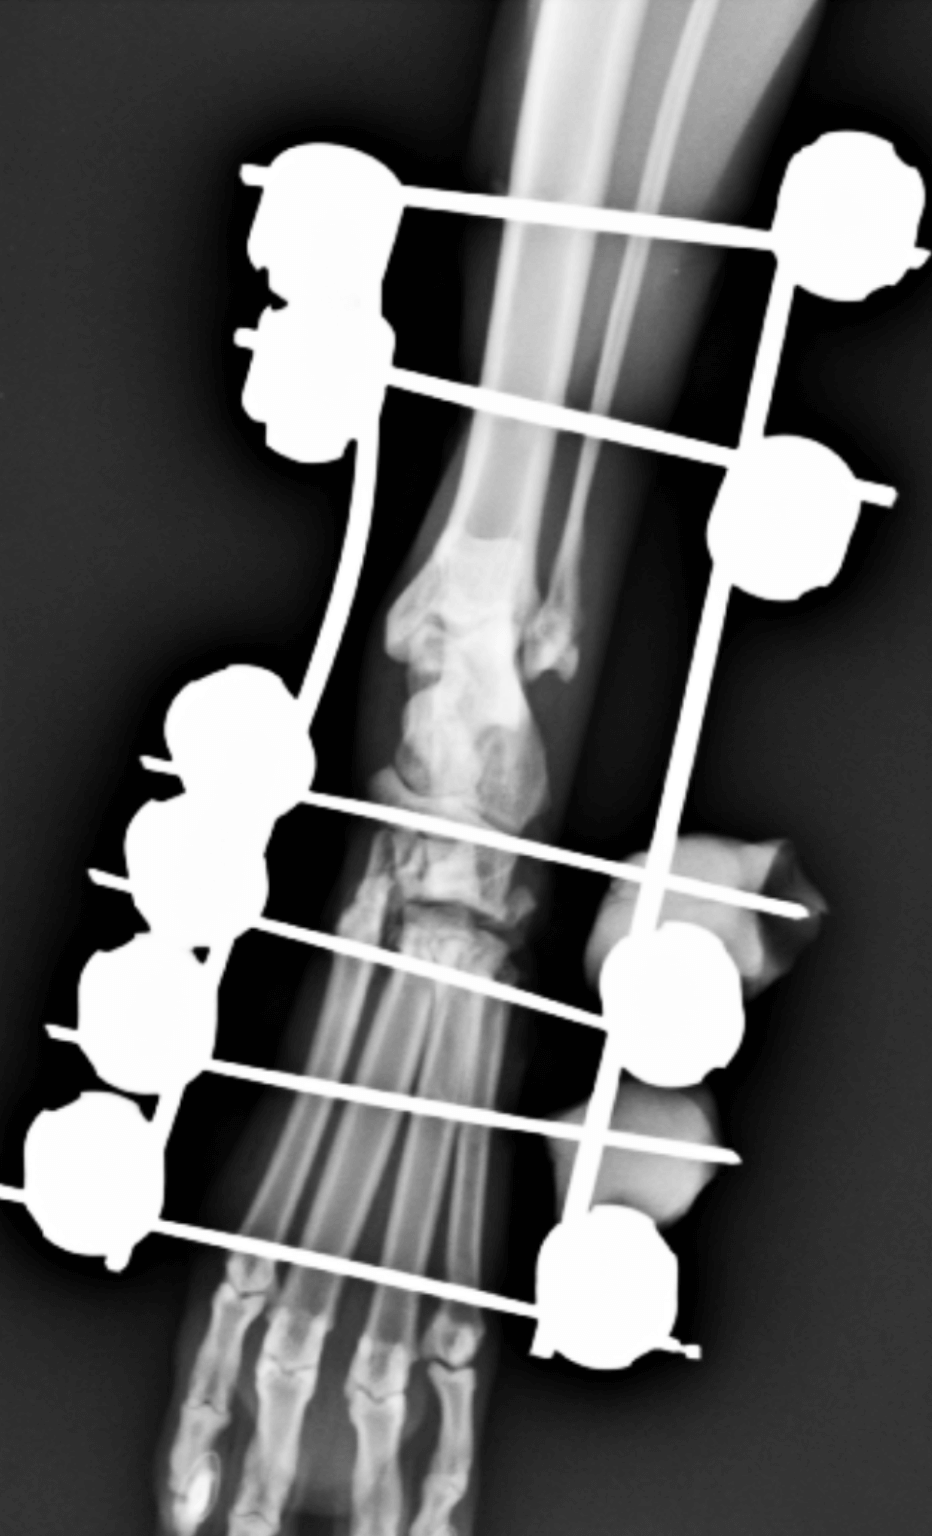

Arthrodèse du tarse chez Nahia avec sa luxation tarso-metatarsienne ouverte. Vue de face